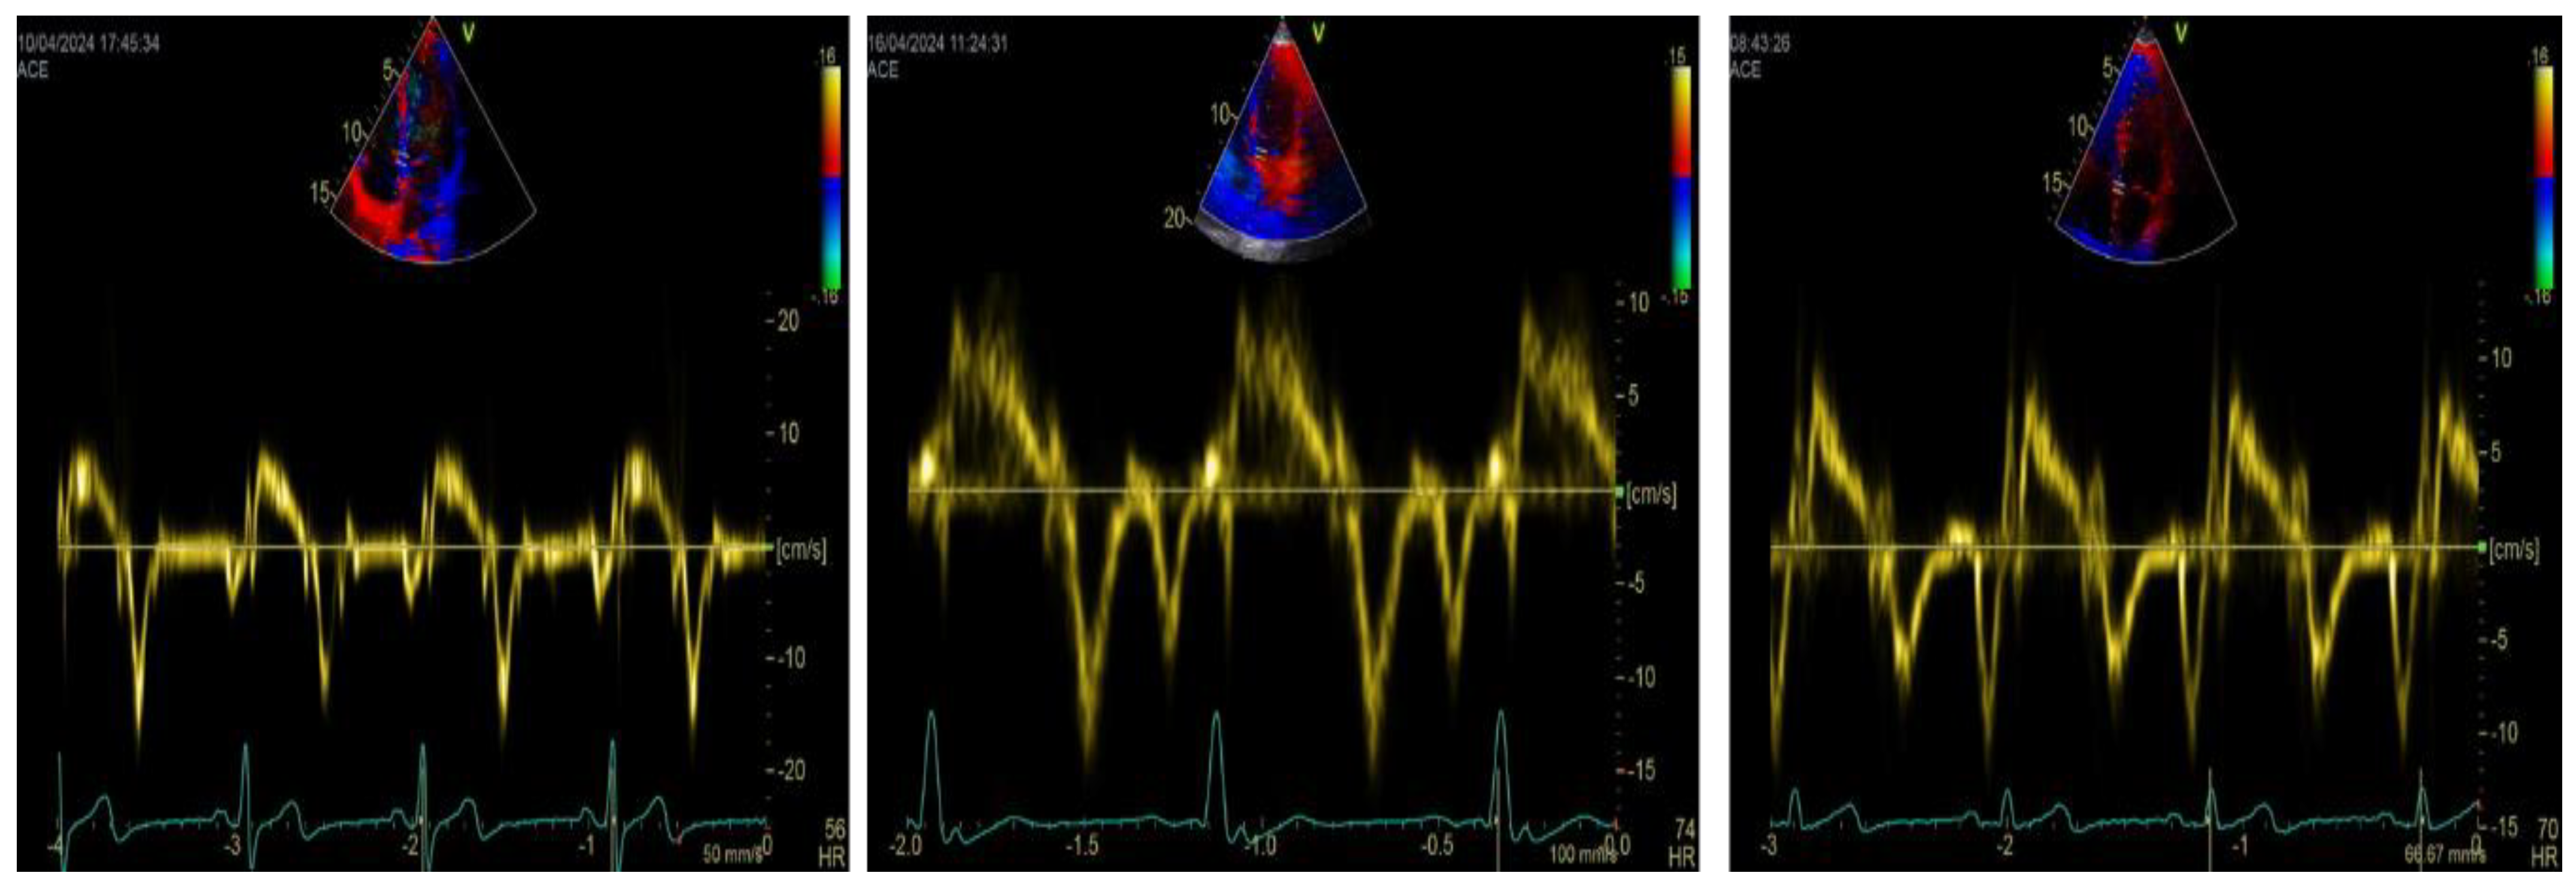

5. Tissue Doppler Imaging and LA Function: A Simplified, Complementary Approach

6. TDI-a’ and Outcome